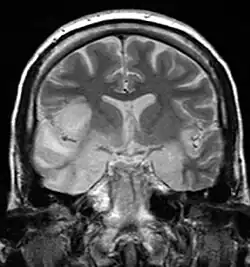

| MRI scan image shows high signal in the temporal lobes and right inferior frontal gyrus in someone with herpes simplex encephalitis. | |